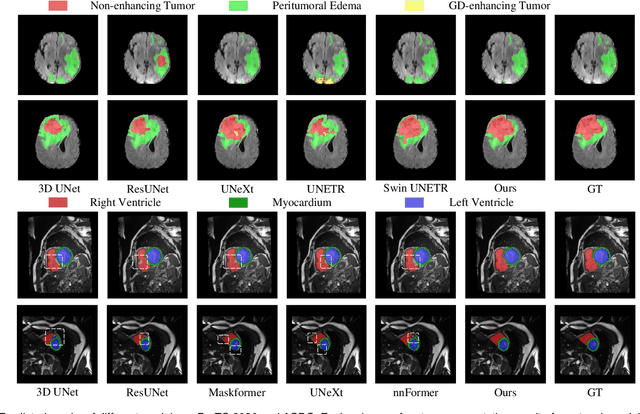

Medical image segmentation is considered as the basic step for medical image analysis and surgical intervention. And many previous works attempted to incorporate shape priors for designing segmentation models, which is beneficial to attain finer masks with anatomical shape information. Here in our work, we detailedly discuss three types of segmentation models with shape priors, which consist of atlas-based models, statistical-based models and UNet-based models. On the ground that the former two kinds of methods show a poor generalization ability, UNet-based models have dominated the field of medical image segmentation in recent years. However, existing UNet-based models tend to employ implicit shape priors, which do not have a good interpretability and generalization ability on different organs with distinctive shapes. Thus, we proposed a novel shape prior module (SPM), which could explicitly introduce shape priors to promote the segmentation performance of UNet-based models. To evaluate the effectiveness of SPM, we conduct experiments on three challenging public datasets. And our proposed model achieves state-of-the-art performance. Furthermore, SPM shows an outstanding generalization ability on different classic convolution-neural-networks (CNNs) and recent Transformer-based backbones, which can serve as a plug-and-play structure for the segmentation task of different datasets.